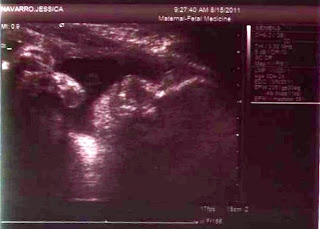

2/24/2011: I didn't bleed anymore all night, but I feel off and on cramping and a mildly painful pressure at my va-j-j. Of course I don't know if that is just normal uterus cramping or miscarriage cramping. I also don't seem to be nauseous this morning, although I took my pills on an empty stomach and within about 10 minutes I was hurling everything back up. Of course this could be nerves from my pending OB appointment today. Our original appointment was 1:30pm, but the stenographer was not going to be there so they rescheduled us for 10:20am. We went in for the sonogram first. I could instantly tell that she was having problems locating anything. I finally asked her if it was "a fake pregnancy". "Is there nothing there?" I asked. She said that I have an enlarged uterus and she was having some difficulty locating the fetus within the sac. Then she said it appeared I had fibroids and that was causing additional difficulty in what she could see. My heart sank and she continued to pillage my uterus. Suddenly there were two sacs! Apparently it was twins!!! One had not properly formed and was not viable, but the second appeared to be ok. She began to take measurements and told us it was tracking at 7 weeks 5 days. We also saw the heart beat! It was just a little flicker, but it looked strong. It was beating 142 beats per minute, which was great. They think the bleeding yesterday was possibly from the first non-viable fetus or possibly just natural spotting; there is really no way to know for sure; but the rest of the exam went very well and everything seems to be progressing normally! The doctor said the second fetus would probably just absorb the first and had we not had the sonogram today, we would have never known about the twin. I didn't even realize twins ran in my family. My grandmother's - father's - mother had twins. Apparently my grandma's cousin also had twins and they are the most recent set. My first OB appointment I weighed 222.2.....I really wanted to ask to take off all my clothes. LOL! The doctor said I needed to spend the next couple of days with my feet up relaxing and then I needed to not be strenuous after that; basically go to work and then go home and lay down. I cancelled my scrapbook retreat for this weekend. I just don't want to risk anything. We were in shock yet again. We prepared ourselves for the worst and never dreamed we would get such wonderful news. I prayed to God for a miracle and the last 24 hours has been pretty rough. God answered our prayers!

3/31/2011: Today was our 2nd official Dr. visit. Today was the "genetic testing". They did a sonogram, this one was exterior on my tummy....wow the baby has grown that much? At almost 13 weeks, I assumed this one would still be vaginal. The baby definitely has Juan's A.D.D. LOL, the baby was constantly rolling and the tech had a bit of a problem getting the baby in the right position. They check for a few things when the do the genetic testing. First they measured the distance of the head to neck, although I don't know how she could tell which was the neck. If it is 3 cm or less, that is a good indicator and our little peep was at 1 cm. They also check for a nasal bone, which our little alien had.....pause on alien. The tech gave us a photo of the profile, which I could totally see and one of the face....which totally looks like an alien! The eyes are like stips vertical and nothing like a baby. So from this point forward, I'm referring to our baby as the little alien. Back to the testing, they also took 5 drops of blood from my finger. The blood test tells them what is the percent likelihood that the baby could have genetic issues; but we won't find out those results for 10 days! Also, based on the last ultrasound the baby should be at 12 weeks, 5 days and the baby today measured 12 weeks, 4 days. The doctor said that she wasn't concerned about the one day difference at all and that everything was green lights and positive. The heartbeat on the sonogram was at 165 beats per minute, although we still couldn't hear it on the doppler externally. The doctor said she wasn't worried as the sonogram is a better test than the doppler and it was probably just a little too soon and we would try again next appointment. My weigh in was 223.6, only 1.5 lbs up from the appointment a month ago and I ate lunch right before my appointment so that is also good. Doc also said it was ok to stop taking the progesterone! It's just crazy thinking there is a baby inside me growing.

5/16/2011 - We had our level II sonogram for "advanced maternal age" today. We also found out it's a GIRL! She is 10oz and everything is perfect. She is in the 30th percentile and the doctor indicated that anything over the 10th percentile is normal. During the sonogram, Juan said, "Is that a vagina?" the doctor sort of skirted his question and then a few minutes later said, "Yes, daddy, it is a girl." Right after that I looked over at Juan to see him frantically texting on his phone. He literally missed the rest of the sonogram because he was too busy spreading the word. After the appointment, he said, "She did have two arms and two legs, right?" I replied, "Yes, and two ears." He replied, "She didn't show us her ears." Too which I responded, "Yes she did, you were just too busy texting to pay attention!!!" Needless to say, he is very excited. I was too. After we left, I couldn't stop bawling. I was just so happy that everything was ok. After all the packing and straining over the past week and a half, I was really worried that something would be wrong. I also don't think I really thought it was going to happen until they told us it was a girl. Now it sort of seems real. As we were driving around after the appointment, Juan says, "Oh my gosh, our baby is part mexican, part white....she's a little coconut! We should call her Coco!" We are NOT naming our baby Coco, but that has quickly become her nickname.

8/15/2011 Today was our follow up Maternal Fetal medicine sonogram for my "advanced" maternal age with Dr. Koster. Everything is tracking beautifully with Madalynne! Her head is sized at exactly 32 weeks, her limbs are tracking at exactly 32 weeks and her belly is tracking at 33 weeks. There is plenty of fluid around her and she has already turned head down preparing for her entrance into the world. She is perfectly average, which is something I never thought I would love to hear! She is measuring 4-1/2 lbs, again perfectly on track. We began discussing the concern with preclampsia as my mother and sister both had it. She said that early indicators for preclampsia is actually a small belly. Apparently preclampsia doesn't allow enough nutrients to get to the baby. The baby takes what she can, which goes directly to her brain and extremities, not leaving enough for her tummy and essentially forcing a baby diet. With preclampsia, the baby's tummy is actually undersized, so the fact that Madalynne's belly is tracking a week larger is actually good. She is healthy.